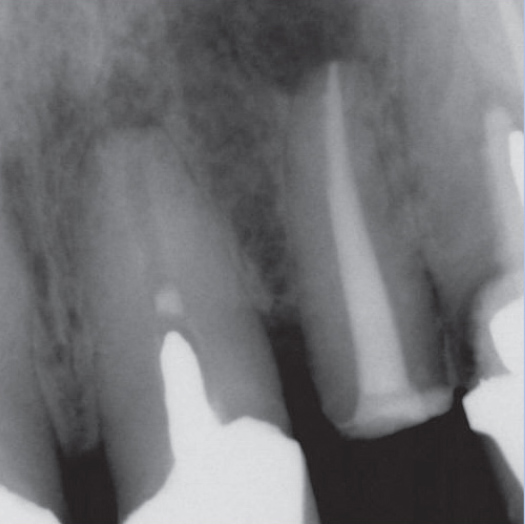

After

After Root Canal treatment